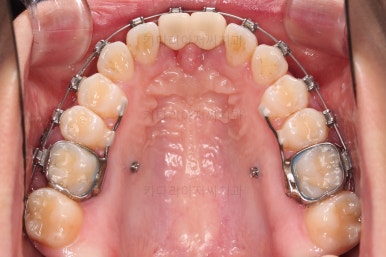

1. 초진

부산개방교합 키다리아저씨치과에 처음 내원 시 입안의 모습입니다.

전반적으로 치열이 삐뚤고요.

앞니쪽이 다물어지지 않는 개방교합(오픈바이트, open bite) 을 보였습니다.

어금니 맞물림을 보면 앵글씨 2급 부정교합 양상이어서 위아랫니가 모두 1대1로 부딪히고 있는 상태였습니다.